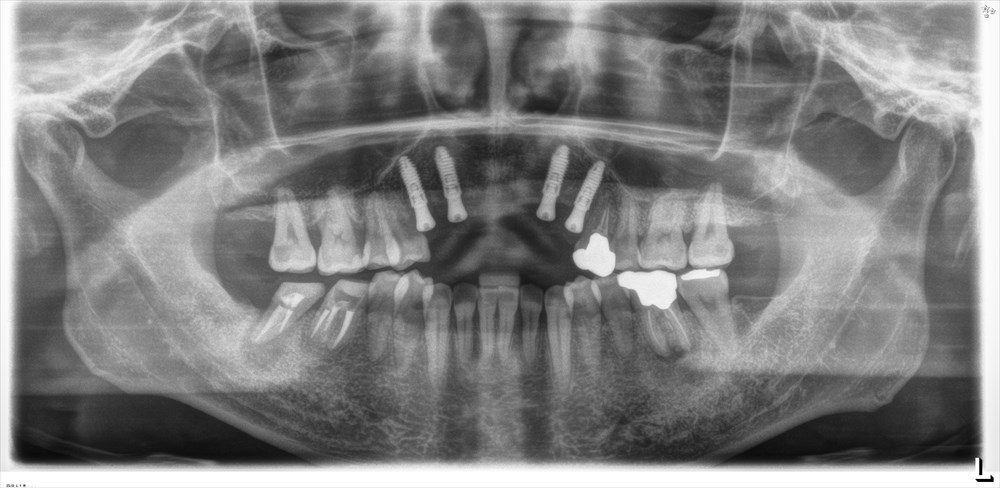

初診は2年前です。

全体的な重度歯周病でした。

前歯だけではなく奥歯も重度歯周病

残念ながら上の前歯は保存が出来ませんでしたが他は歯周基本治療(MINST)を私が行い

治しました。

歯周外科は行わず基本治療(歯茎を切らずマイクロスコープのみ)で

すべて3mm以内のポケットになっています。

この時点で無切開のインプラントを上の前歯に入れました。